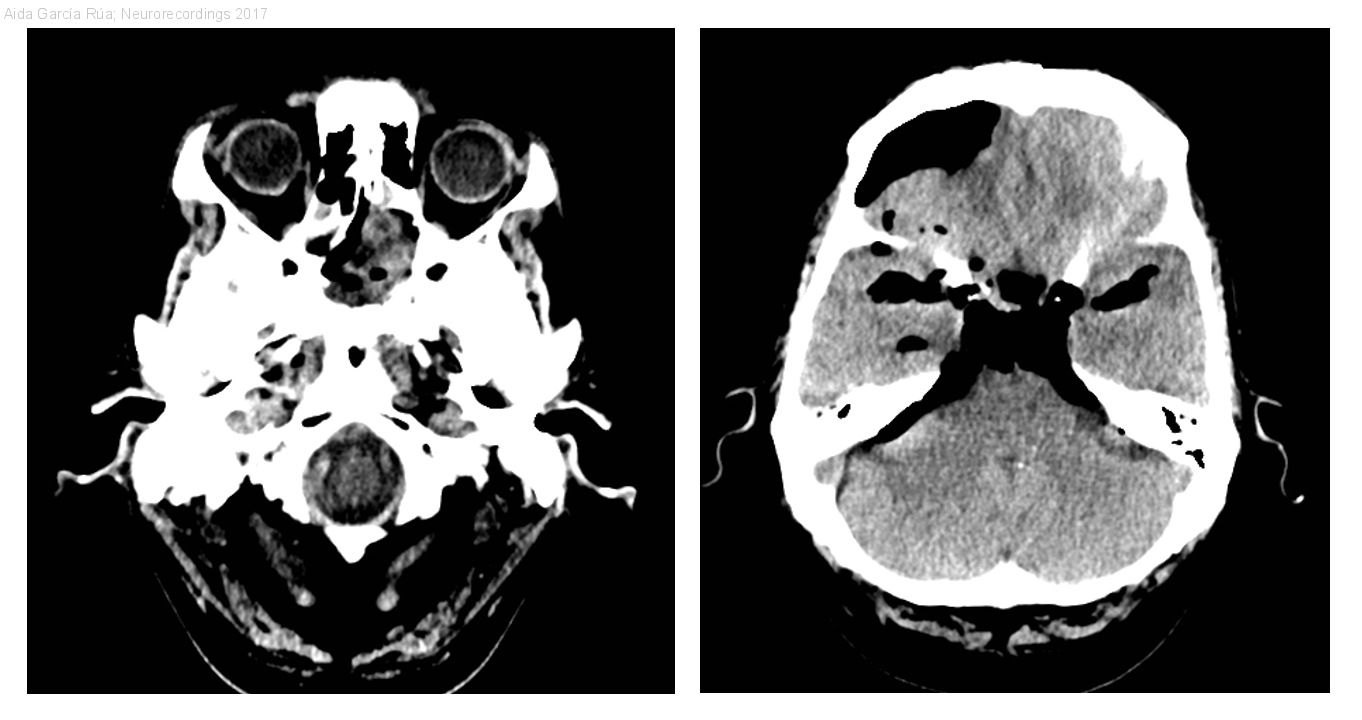

Diagnóstico final: Neumoencéfalo secundario a fístula de líquido cefalorraquídeo espontánea

Cuadro catarral con tos persistente de varios días de evolución, complicado con cefalea holocraneal progresiva y finalmente deterioro del nivel de conciencia. A la exploración encontramos una paciente afebril, tendente al sueño y desorientada, sin...